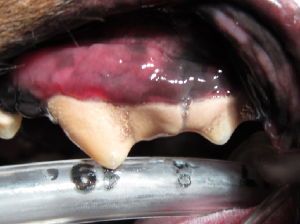

一番左の画像は歯石を取る前ですが、この時点で歯周ポケットはあまり存在しないだろうという予想を立てます。実際、麻酔下においてポケットを計測しても近心遠心ともに3mmのポケットであり、さほど重症度は高くないと判断されます。しかし下記をご覧いただくと

同様に頬側は正常で口蓋側のポケットが深い例です。

歯間に食事の残りかす、および、毛が大量に挟まっております。中等度の歯肉退縮がみとめられます。本例においては、レントゲンおよび視診により、治療可能と判断しました。

基準の一つとして、歯肉粘膜境界部を超えていないという事になります(青のトレース)。これを超えている場合(現在の青のラインよりより上方)でも当院では治療にすすみますが、治癒率が格段におちます。また黄緑が正常の歯肉のラインとなります。

同犬種における正常な歯肉ライン。

歯石除去、ペリオ用超音波による治療、ルートプレーニング、部位によってはEMD(エナメルマトリクスタンパク)、縫合をします。(画像は下顎)